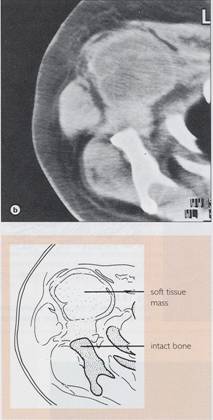

- CT & RMN apreciaza extinderea os si

extracompartimentala a tu

Chondrosarcom

b)humerus dr

proximal, distructie corticala, extensie in parti moi